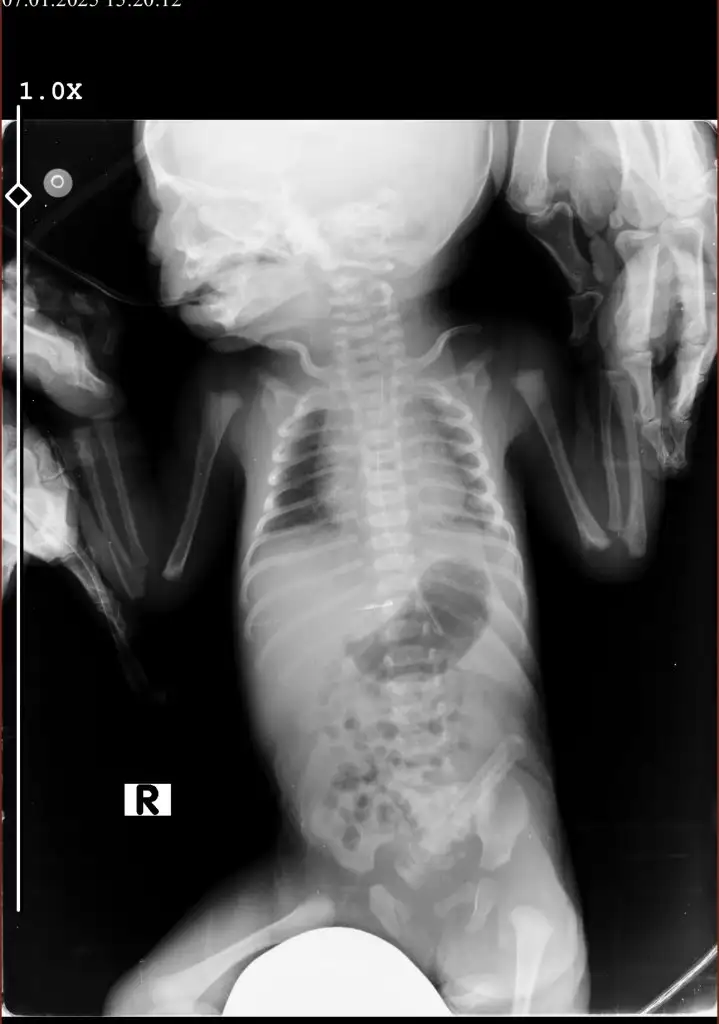

Sol tarafta beyazlıklar var ya onun bir kısmı kalbin gölgesi ama yine de yukarı doğru biraz beyazlık var yani oralara oksijen gitmemiş. Şimdi entübe edildiği için basınçla oraya oksijen verecekler ciğerleri toparlanacak. İlaç tedavisi ile de iltihap gerilecek inşallah. Biraz zayıf mı doğdu haftasıyla uyumlu muydu evladınız ?

2430 gram doğdu haftasıyla uyumlu dediler sizce iyileşir mi doktor da verdiğimiz antibiyotikle orayı kapatmaya başladık dedi bebekler büyüklere göre daha hızlı iyileşiyor dedi Allahtan ümit kesilmez dua ediyorum hep inşallah düzelir görmeye gidiyorum her gün 5 dk izin veriyorlar

Maşallah ona doktorunuz ne diyorsa onun dediği doğrudur emin olun en kötü ihtimali söylerler. Susuz doğan bebeklerde bu durum olması normal çünkü su bebeği koruyan mucizevi bir şey. O yüzden dualarınızı eksik etmeyin sabredin bebekler çok güçlü. İnşallah iyi olacak ciğerde çok hasar yok öyle diyeyim ama elbette her an herşey de olabiliyor olumsuz düşünmeyin bir an önce sağlıkla kavuşun inşallah. Kendinizi üzmeyin bebeğiniz hala size bağlı hala sizi hissediyor. İyileş gel annecim iyi olacağız seni çok seviyorum bak odanı hazırlıyorum bak kıyafetlerini hazırlıyorum gibi olumlu cümleler kurun yanına gittiğinizde konuşun ağlamayın olur mu ne kadar güzel olduğunu söyleyin :)